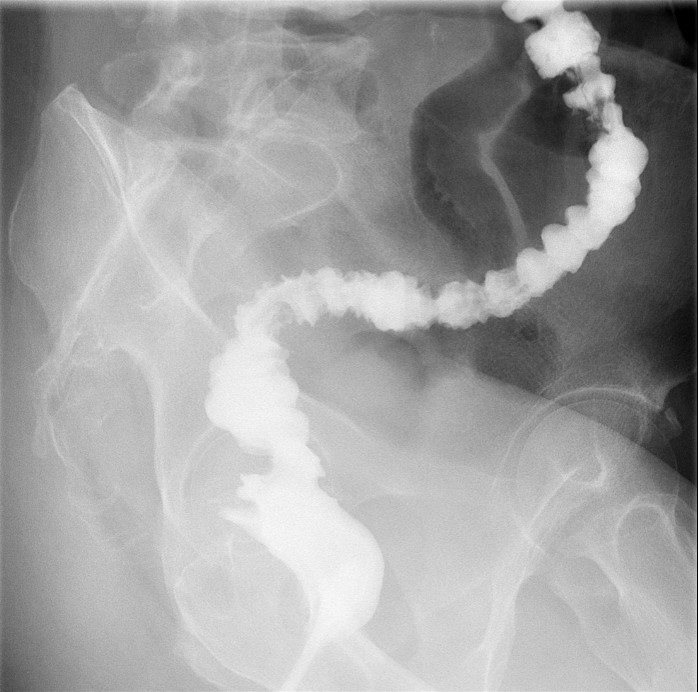

- Obtain images of the terminal ileum and the ileocecal valve filled with contrast material

(key image 6)

(key image 7)

(key image 8)

(key image 9)

(key image 10).

- Obtain spot images of the remainder of the small bowel

(key image 11)

(key image 12)

(key image 13)

(key image 14).

- Obtain images of all four quadrants. Use the compression paddle to separate loops of small bowel from each other.